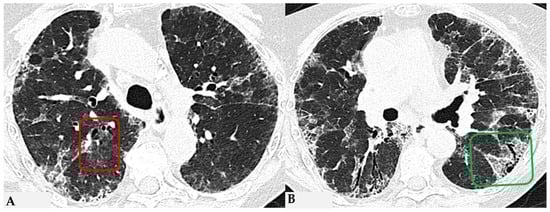

HP, as extensively described, represents a diffuse infiltrative disorder caused by sensitization to inhaled antigens that trigger an exuberant and abnormal immune response in the bronchial and alveolar regions of the lungs. Disease susceptibility is regulated by host-related factors, including genetic variations influencing immune response, as well as antigen properties and exposure-related factors. A cluster of patients with fibrotic ILDs, particularly those with FHP and those with CTD-ILDs, show a susceptibility to developing a progressive fibrosing phenotype despite proper therapeutic management: “Progressive Pulmonary Fibrosis” (PPF-ILD) [24,25]. Literature data estimate that approximately 18–32% of patients diagnosed with non-idiopathic fibrotic ILD (non-IPF) may progress towards a progressive phenotype with unfavorable outcomes [26]. This progressive cluster includes different pathologies that share some markers of fibrogenetic activation, showing remarkable similarities with the clinical course observed in aggressive IPF, a prototype of unfavorable prognosis in fibrotic ILDs. Shared pathogenetic mechanisms cause collagen matrix deposition, distorting interstitial architecture and leading to advanced fibrotic damage. This results in a progressive decline in lung function, exacerbated symptoms like dry cough and dyspnea, nutritional deficits and an overall decrease in quality of life. In some cases, this can lead to treatment refractoriness and early mortality. From a genomic perspective, advancements are being made in the search for in vivo biomarkers (liquid biopsy: evaluation of biological fluids such as saliva, sputum, blood, urine, tissues, etc.) with assessment of genomic, proteomic and metabolomic profiles. This would allow for a much more detailed stratification of patients with ILDs in general and those with progressive fibrotic forms in particular [27,28]. This would enable a multimodal cross-sectional approach to understand markers that can further explain aspects of physical decline capable of influencing patient nutrition, thus accelerating physical decline [29]. For this reason, the new aspects related to the decoding of “omics” markers could impact significantly new therapeutic profiles. From a purely radiological standpoint, the new guidelines on IPF and progressive forms make it evident how the role of HRCT evaluation in patients diagnosed with fibrotic ILD can be indispensable in the “timing of serial assessment”, with accurate longitudinal evaluations and side-by-side visual comparison of HRCTs, integrating clinical and functional data and demonstrating possible progression (Figure 13). No standardized protocols exist for treating HP. Prioritizing antigen avoidance is crucial. Though immunosuppressants are frequently employed, their efficacy in slowing fibrotic disease progression remains unproven. The US Food and Drug Administration has sanctioned Nintedanib, a tyrosine kinase inhibitor, for impeding the advancement of chronic fibrosing ILDs, encompassing the progressive fibrotic form of HP. Non-pharmacological measures like oxygen therapy, pulmonary rehabilitation and supportive care play pivotal roles in the comprehensive management of individuals with progressive HP. The new therapeutic frontiers, therefore, open significantly encouraging scenarios in patients with progressive forms, as even these secondary fibrosing forms, previously orphaned of therapy due to their evolutionary characteristics, can finally benefit from antifibrotic therapy like idiopathic forms.

Figure 13.

Progressive FHP pattern. Axial chest HRCT scan. Longitudinal assessment of a rapidly progressive form of HP: evident transitions from a cellular form characterized by GGO/centrilobular fluffy nodules and mosaic attenuation (A) to a fibrotic form (B), characterized by distorted fibrotic GGO, traction bronchiectasis and bronchiolectasis (blue shape), a clear increase in the extensive area of air trapping on the right (yellow circle) and an area of lung spared from the pathological process (red box): a picture of progressive FHP with a “three density pattern”.